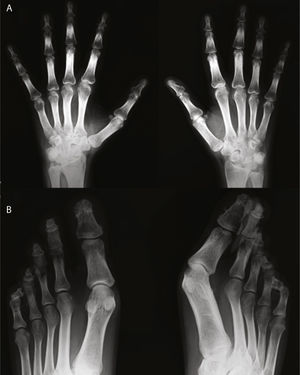

Presentación clínicaVarón de 30 años de edad, diagnosticado de hipertensión arterial pulmonar primaria sin cortocircuito asociado a los 2 años de edad, en seguimiento por Cardiología Pediátrica desde entonces. No tenía otros antecedentes médicos personales ni familiares de interés, incluyendo enfermedades reumáticas y psoriasis. A los 29 años comenzó a presentar episodios de poliartritis simétrica y aditiva que afectaban rodillas, tobillos, hombros, carpos y metacarpofalángicas, con importante limitación funcional. En la exploración física destacaba además la presencia de cianosis generalizada y acropaquias, sin lesiones cutáneas ni ungueales sugestivas de psoriasis. En la analítica se evidenció reactantes de fase aguda normales, factor reumatoide negativo y anticuerpos anti-CCP positivos a título bajo en una determinación aislada. El estudio radiográfico mostró acro-osteolisis en falanges distales de manos y pies, más severa en esta última localización, en la que algunas falanges adoptaban una morfología piramidal o con el extremo aplanado, y en ambas localizaciones existía importante neoformación ósea, más marcada en manos (figs. 1 y 2). En ambos carpos se observaba además pinzamiento radiocarpiano y de articulaciones intercarpianas, mayor en el izquierdo, sin erosiones. En huesos largos (tibias, peronés y radios) se evidenciaban corticales de aspecto algodonoso y despegamiento perióstico compatibles con periostitis. La gammagrafía ósea mostraba moderada hipercaptación en falanges distales de ambas manos, así como carpo y radio derechos y zona teórica de semilunar izquierdo.

Radiografía de manos (A) en la que se observa reacción perióstica en radio. Ensanchamiento distal con cambios hipertróficos en los penachos y áreas de osteolisis en los mismos, de las que es un buen ejemplo el cuarto dedo de la mano derecha. Desmineralización yuxtaarticular. Radiografía de pies (B) en la que se observan marcados cambios destructivos en falanges distales, algunas con morfología aplanada y penachos distales hipertróficos con proliferación ósea. Marcada deformidad de los dedos en palillo de tambor.

En estudios previos se ha descrito que la afección de pies es más frecuente y de mayor severidad que la de las manos1,4, al igual que lo ocurrido con nuestro paciente. También es un hallazgo radiológico característico la aparición de reacción perióstica sólida y continua en las diáfisis de huesos largos3, como en las tibias y en el radio de este paciente.